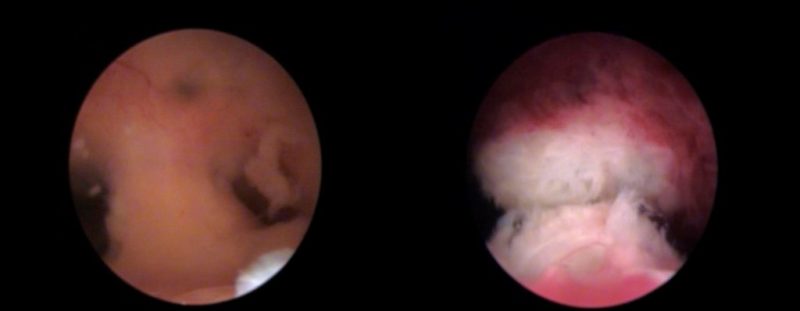

Nueva unidad IB para el diagnóstico y tratamiento reproductivo del Síndrome de Asherman

«Tratamientos a la medida de las necesidades reales», bajo esta premisa inherente en nuestra manera de trabajar y cuidar de nuestros pacientes, hemos diseñado, dentro de la Unidad de fallo de implantación y aborto de repetición del Instituto Bernabeu.